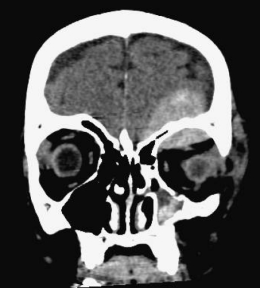

fracture du canal optique gauche avec rhinorrhée droite du fait de l’asymétrie de la cloison du sinus sphénoïdal - étage postérieur : correspondant à la face postérieure du rocher, il est en rapport avec l’oreille moyenne et les cellules mastoïdiennes, ces dernières ont la particularité de ne pas avoir de muqueuse.

mère (Cf. ci-dessus) ; en effet, la dure-mère est très adhérente à l’os au niveau des sutures, notamment fronto-ethmoïdale, ce qui est illustré par les rares hématomes extra-duraux du toît d’orbite (Cf. ci-contre). en cas de fracture il y aura donc déchirure durale et non décollement en regard de la suture.